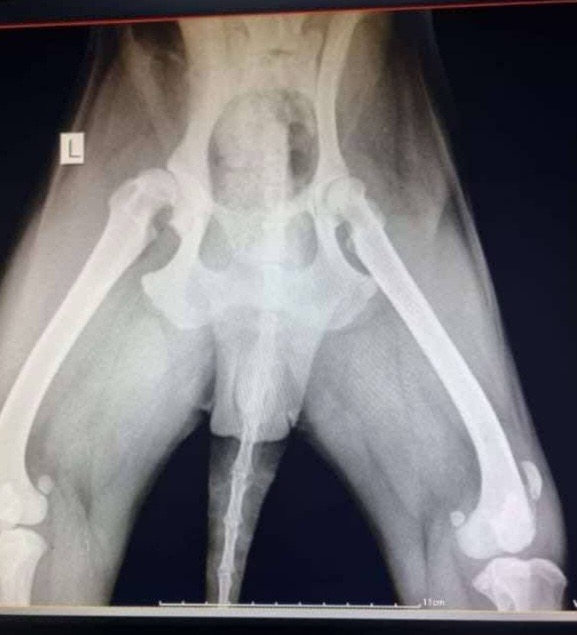

Lizzy came to the shelter last year and we could see she had a limp. She was x-rayed and it was discovered she has quite bad hip dysplasia which is meaning she has a bad limp as well as osteoarthritis on the left side.